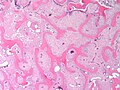

Fibrous dysplasia. H&E stain. | |

| LM | woven bone with odd irregular shapes (often described as "chinese characters"), fibrous tissue around bone, no osteoblastic rimming |

- Woven bone with odd irregular shapes - key feature.

- Described as "chinese characters".[2]

- Fibrous tissue around bone.

- No osteoblastic rimming.